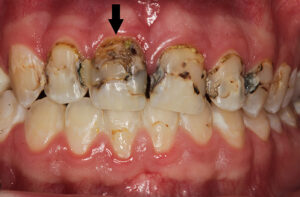

Hier sieht man das Problem:

Karies – Durch Karies können Zähne so stark zerstört sein, dass diese nicht mehr mit einem Zahnersatz versorgt werden können. Auf dieser Abbildung war der rechte zentrale Schneidezahn (schwarzer Pfeil) nicht erhaltungsfähig. Die anderen kariösen Zähne konnten durch aufwändige Maßnahmen noch erhalten werden.